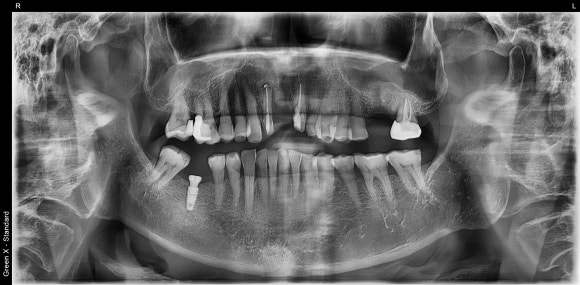

20241026

계단도 없는 저희 치과에 매번 혼자서 씩씩하게 오시는 80대의 어르신 환자분입니다.

정말 건강하십니다.

오른쪽 아래 어금니가 빠진지 여러 해가 되어

앞 뒤 치아들이 조금씩 빈공간을 향해 쓰러졌습니다.

그 탓에 어금니가 있었던 공간이 점점 좁아졌지요.